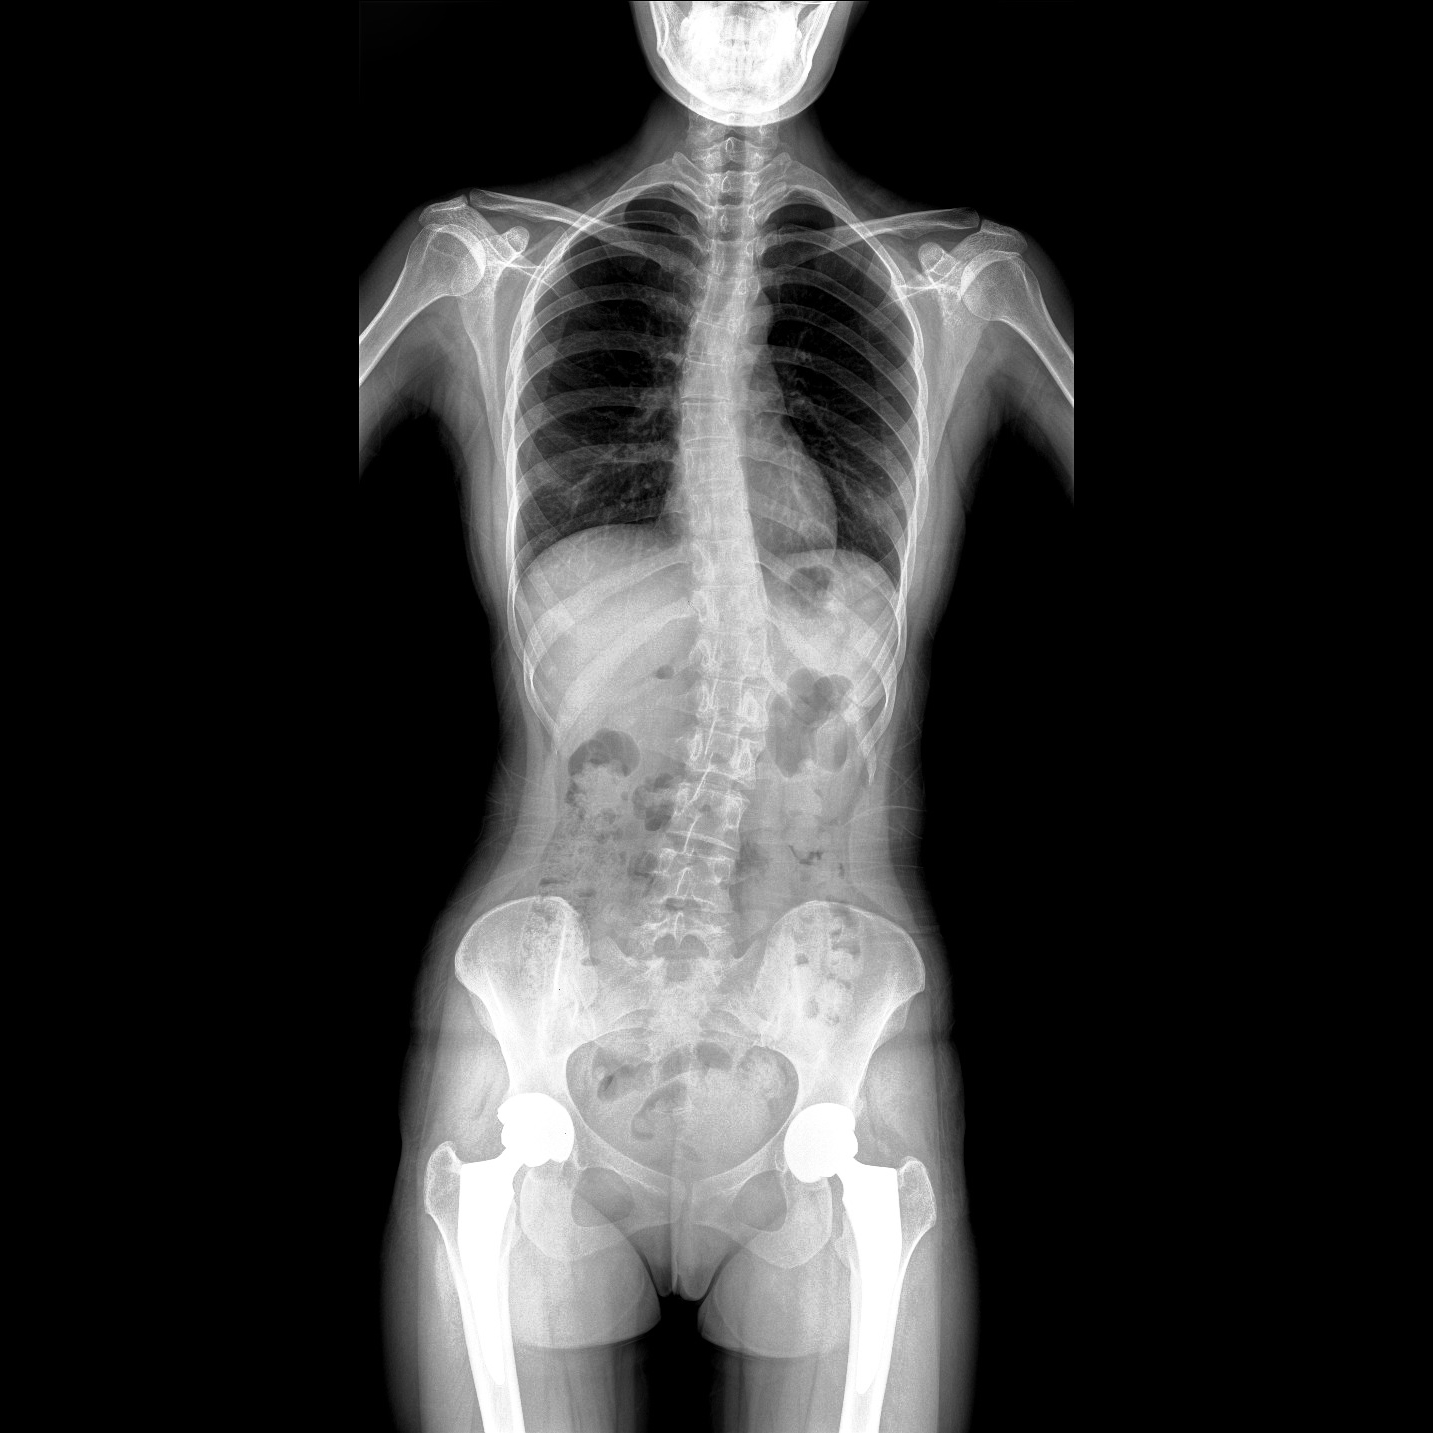

支持全脊柱攝影、雙下肢攝影、脊髓造影、復(fù)雜創(chuàng)傷、人工關(guān)節(jié)置換、關(guān)節(jié)損傷的修復(fù)重建等大視野臨床應(yīng)用

全脊柱一次成像 不拼接

17"*34"有效視野,一次成像不拼接。相較于多張攝影再軟件拼接的DR設(shè)備,PLX8600解決了拼接圖像存在密度不均勻,拼接處圖像配準(zhǔn)和放大效應(yīng)等問題,給臨床帶來了大視野影像解決方案,可一次性覆蓋全脊柱或雙下肢影像。

Clinical picture

臨床圖片